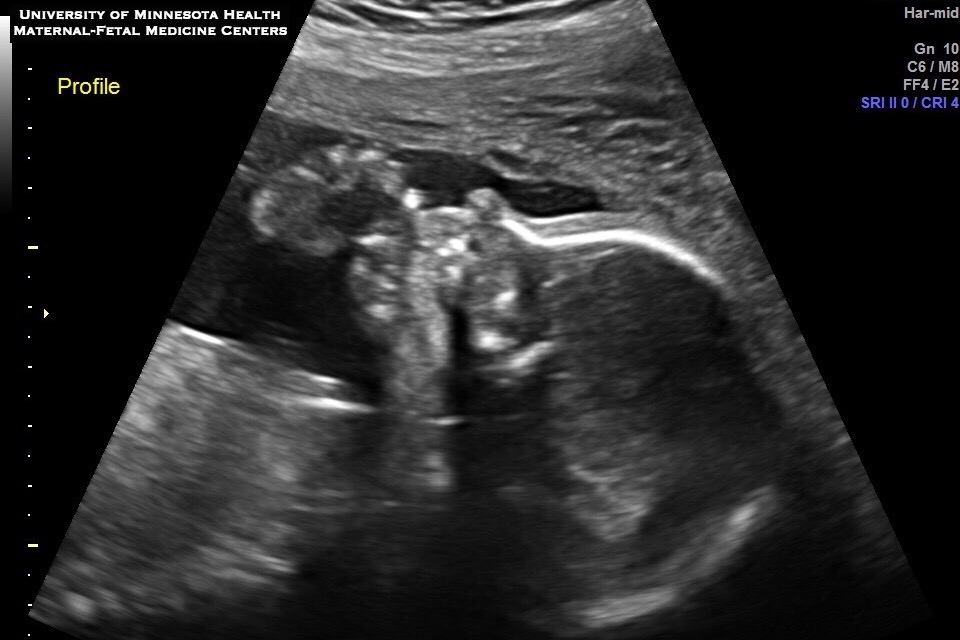

They went in for their 20 week ultrasound and got some news that was very upsetting but at the same time a blessing to find early. Nikki was diagnosed with Velamentous Cord Insertion, low lying Placenta and Vasa Previa, a rare condition with only 1 in 2500 births.

These are very serious complications. To simply explain, a Velamentous Cord Insertion and Vasa Previa are pregnancy complications in which the umbilical cord is abnormally inserted into the placenta and blood vessels run close to the inner part of the cervix. Due to this, baby’s blood vessels are unprotected by Wharton’s Jelly and no longer tucked inside the umbilical cord. Instead, they are low lying running next to or over the cervix.

Luckily the ultrasound tech caught this problem and there is a 97% success rate as long as it’s caught early.